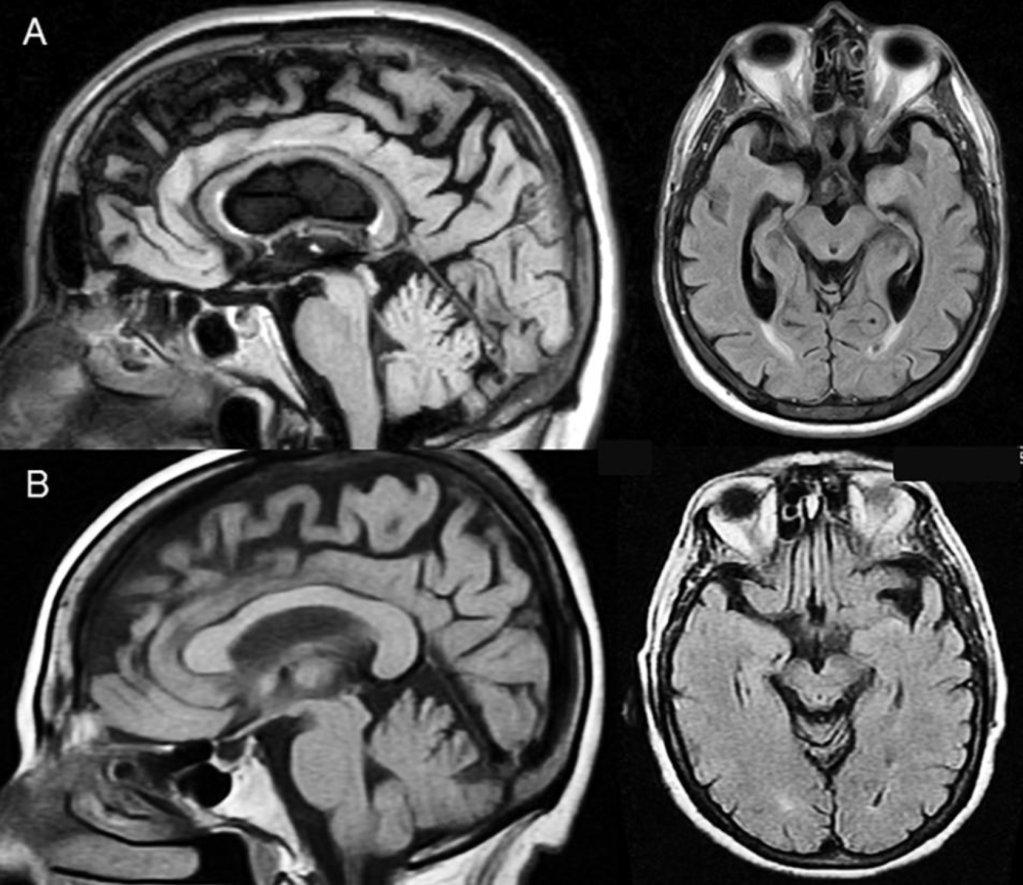

En las afasias asociadas a EVC, la ecolalia puede ocurrir no sólo como consecuencia de una lesión frontal “liberadora” del circuito perisilviano, sino también de forma secundaria a lesiones posteriores profundas que desorganizan la red neuronal de lenguaje. En el caso descrito por Abusrair y AlSaeed, la imagen de difusión muestra un infarto en el lóbulo parietal inferior izquierdo, regiones parietooccipitales, cápsula interna y esplenio del cuerpo calloso, es decir, en un sitio neuroanatómico crítico donde convergen fibras de asociación y proyección que conectan áreas temporoparietales con otras regiones del hemisferio y con el hemisferio contralateral. Esta afectación no destruye por completo la maquinaria perisilviana de repetición, pero sí altera la integración entre percepción auditiva, procesamiento semántico, control motor del habla y redes interhemisféricas, generando una imagen clínica en la que la repetición queda relativamente preservada mientras el lenguaje espontáneo y la comunicación eficaz se ven afectadas. La ecolalia, en este contexto, puede leerse como un eco que rebota en un sistema parcialmente desconectado: las palabras ajenas siguen encontrando la vía para ser articuladas, aunque se pierde la interlocución para generar un discurso coherente de dos vías.